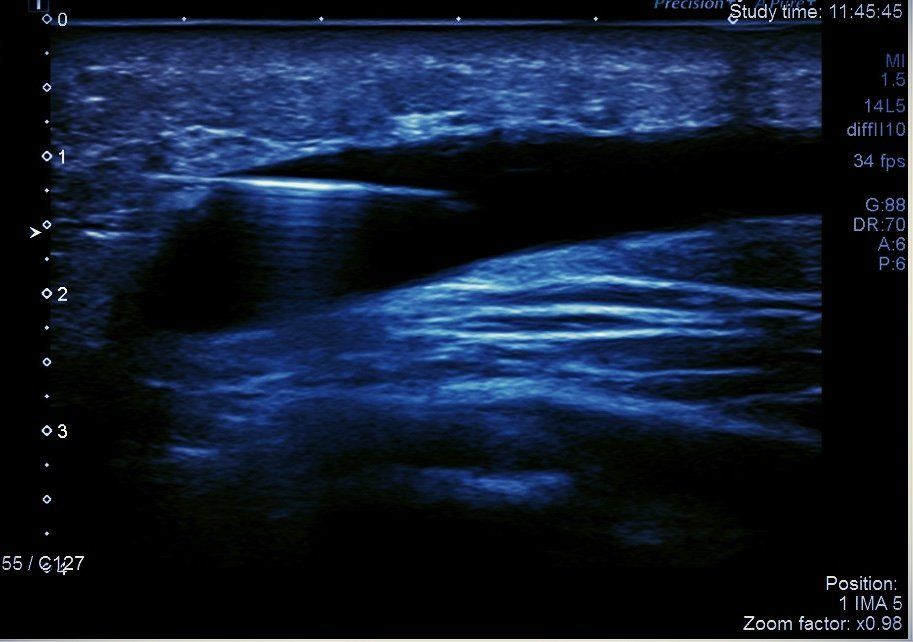

La ponction s'effectue sous contrôle échographique constant et avec un matériel stérile.

- Mise en place de l’aiguille au sein de la calcification

- Injection sous pression de sérum physiologique stérile

- Recueil du mélange sérum + calcium (ou “boue calcique”)